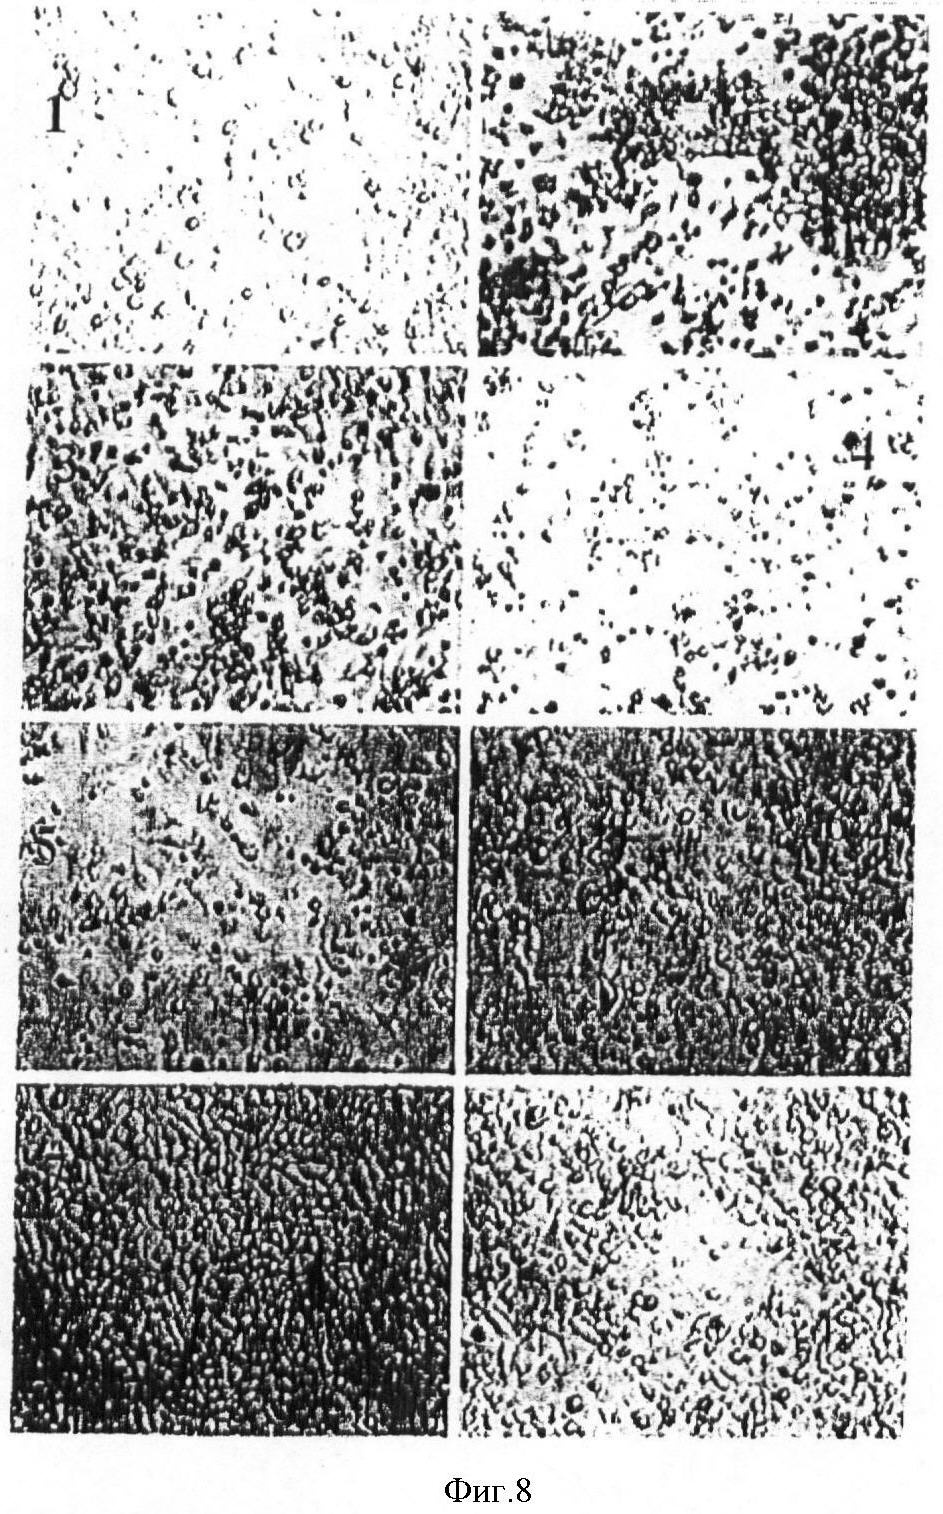

На фиг.8 показаны микрофотографии клеток Hep-2 спустя 36 ч после того, как их инфицировали рекомбинантом р53 аденовируса. 1 – контроль; 2 – MOI 200; 3 – MOI 150; 4 – MOI 100; 5 – MOI 50; 6 – MOI 10; 7 – вирус GFP MOI 200; 8 – вирус GFP MOI 150;

Эффект цитолиза рекомбинанта р53 аденовируса на клетки опухоли:

клетки Нер-2 подвергли трансфекции рекомбинанто аденовйрусом р53 стандартным способом.

В каждой из групп клеток их подсчет проводился одинаково. Клетки были разделены на следующие группы: 1 – контрольная эталонная группа; 2 – MOI (множественность заражения) 200; 3 – MOI 150; 4 – MOI 100; 5 – MOI 50; 6 – MOI 10; 7 – вирус GFP MOI 200; 8 – вирус GFP MOI 150. Клетки инкубировали 36 ч после проведения трансфекции. Эффект цитолиза рекомбинанта р53 аденовируса на клетки опухоли можно было наблюдать под микроскопом при множественности заражения, составляющей не более 50. Указанный эффект возрастал с ростом дозировки. Под микроскопом наблюдалось сморщивание клеток и их окрашивание. Полученные результаты приведены на фиг.8.